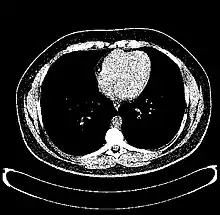

The Hounsfield scale (/ˈhaʊnzfiːld/ HOWNZ-feeld), named after Sir Godfrey Hounsfield, is a quantitative scale for describing radiodensity. It is frequently used in CT scans, where its value is also termed CT number.

Values for different body tissues and material

HU-based differentiation of material applies to medical-grade dual-energy CT scans but not to cone beam computed tomography (CBCT) scans, as CBCT scans provide unreliable HU readings.[6]

Values reported here are approximations. Different dynamics are reported from one study to another.

Exact HU dynamics can vary from one CT acquisition to another due to CT acquisition and reconstruction parameters (kV, filters, reconstruction algorithms, etc.). The use of contrast agents modifies HU as well in some body parts (mainly blood).